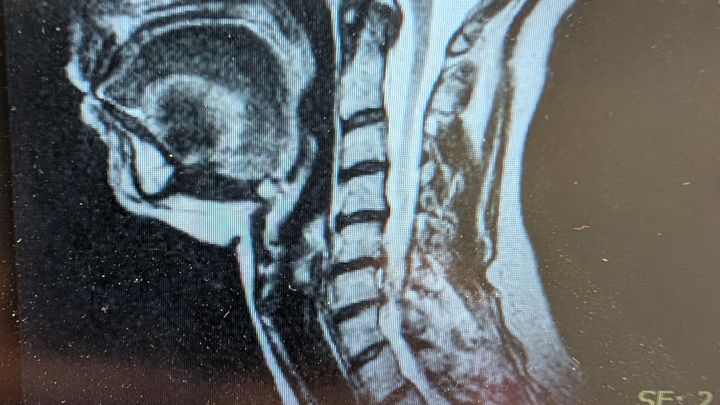

I am facing cervical spine surgery, and I'm raising funds to cover 6 weeks of living expenses! Insurance has my surgery covered, and I have less than 50 hours of PTO, but I need funds to cover the rest of my recovery time since I do not have short or long-term disability. Any and everything will help! Thank you, and God bless!